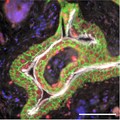

A Germinated Microsporidian Spore in Close Proximity to the Host Cell Surface

Transmission electron micrograph shows a germinated microsporidian spore adjacent to a host cell, with a polar tube extending to transfer sporoplasm into the host cytoplasm. The study identified EnP1, a nucleus-targeted effector secreted by microsporidia, which enhances their proliferation by interacting with host histone H2A and inhibiting ferroptosis. This research highlights how microsporidia alter host cell functions through secreted effector proteins, ultimately facilitating their own survival and contributing to disease progression. Guan et al. 2026

Image Credit: Bing Han